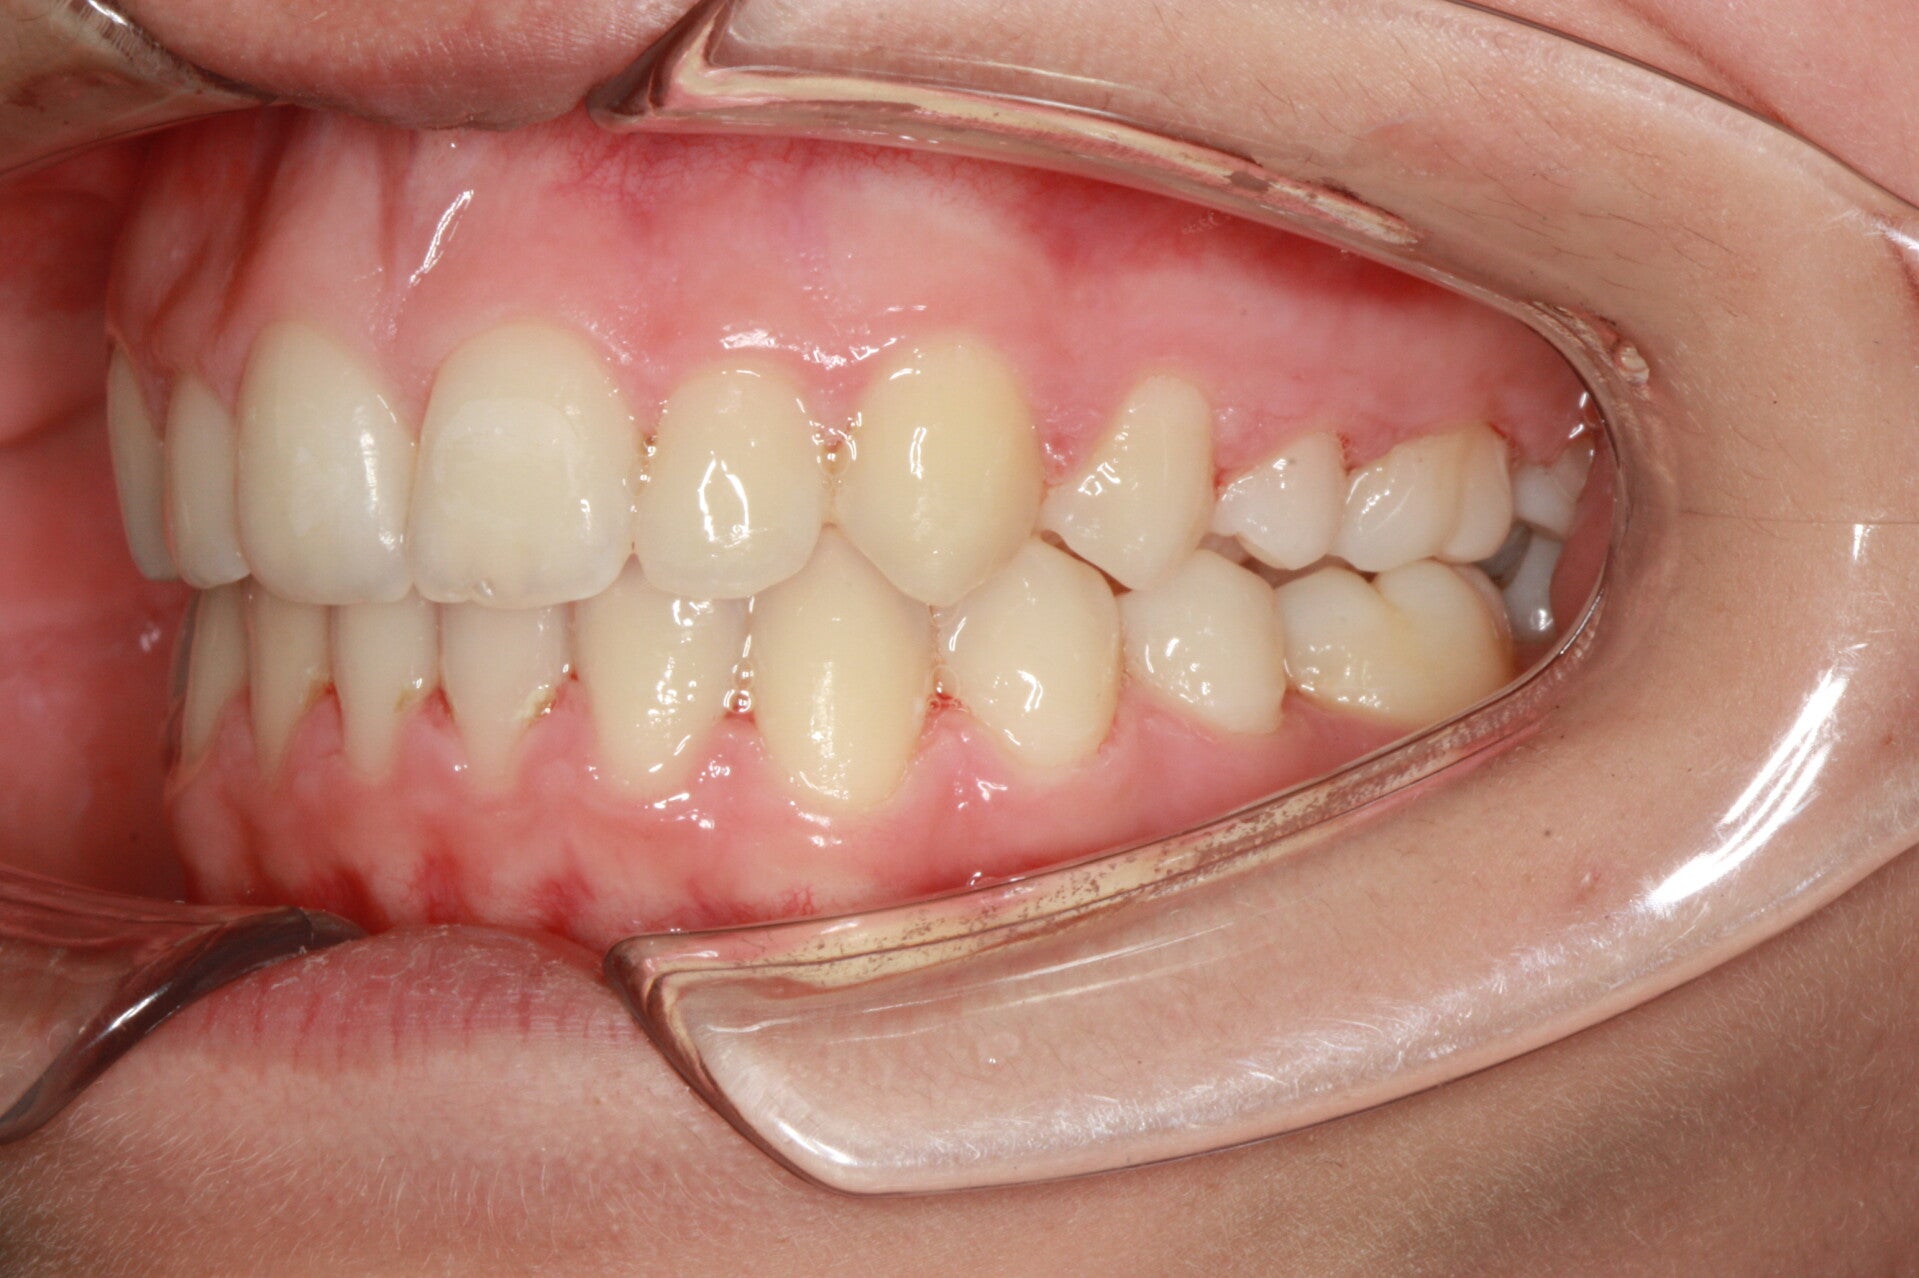

SECONDA CLASSE SUDDIVISIONE DESTRA

Questo mese vi presentiamo G.G. f. di15aa. Ha una seconda classe suddivisione destra molare e canina. richiesta Allineamento.

FOTO FINALI DOPO 24 MESI CIRCA DI TERAPA ORTODONTICA FISSA